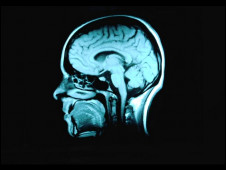

現在,英國和芬蘭的研究人員針對三個大型的有關老年化的研究進行分析,這三個大型研究一共觀察了872名已經去世的老年人的大腦。

研究人員發現,在他們去世之后,他們大腦里出現失智癥的病變,與他們接受的教育程度沒有明顯關系。

但是接受教育程度越高的人,就越能適應老年之后帶來的種種問題,包括記憶力減退。

劍橋大學的漢娜·基格(Hannah Keage)表示,“我們發現在人死后,有的人大腦里出現失智癥病變,但這個人生前卻沒有失智癥癥狀?!?/p>

“研究顯示,接受教育能讓人更好的適應他們大腦老化帶來的問題。”